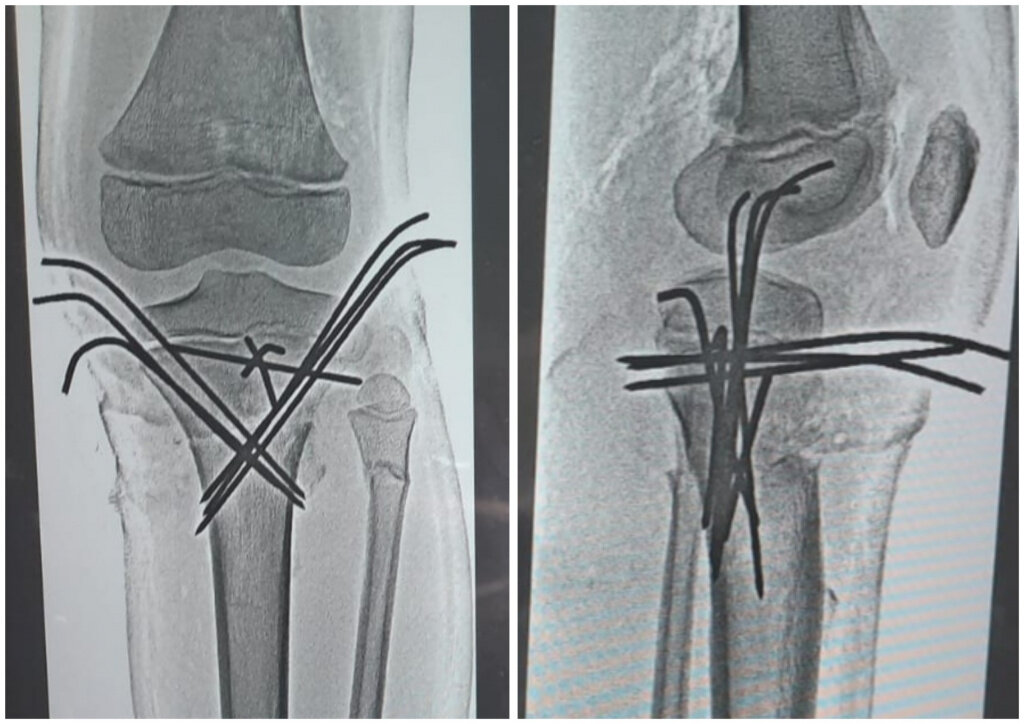

Чтобы поставить мальчишку на ноги и вернуть ему возможность двигаться полноценно, травматологи уже провели 4 этапа хирургических вмешательств, и это не конец истории. Впереди ряд операций по удалению скрепляющих металлических конструкций, которые находятся в конечностях. На снимках видно, что кости пациента напичканы металлом. - Медики делают все возможное, чтобы поставить парнишку на ноги, - говорят в облздраве. Юным пациентом занимаются лучшие специалисты

Чтобы поставить мальчишку на ноги и вернуть ему возможность двигаться полноценно, травматологи уже провели 4 этапа хирургических вмешательств, и это не конец истории. Впереди ряд операций по удалению скрепляющих металлических конструкций, которые находятся в конечностях. На снимках видно, что кости пациента напичканы металлом.